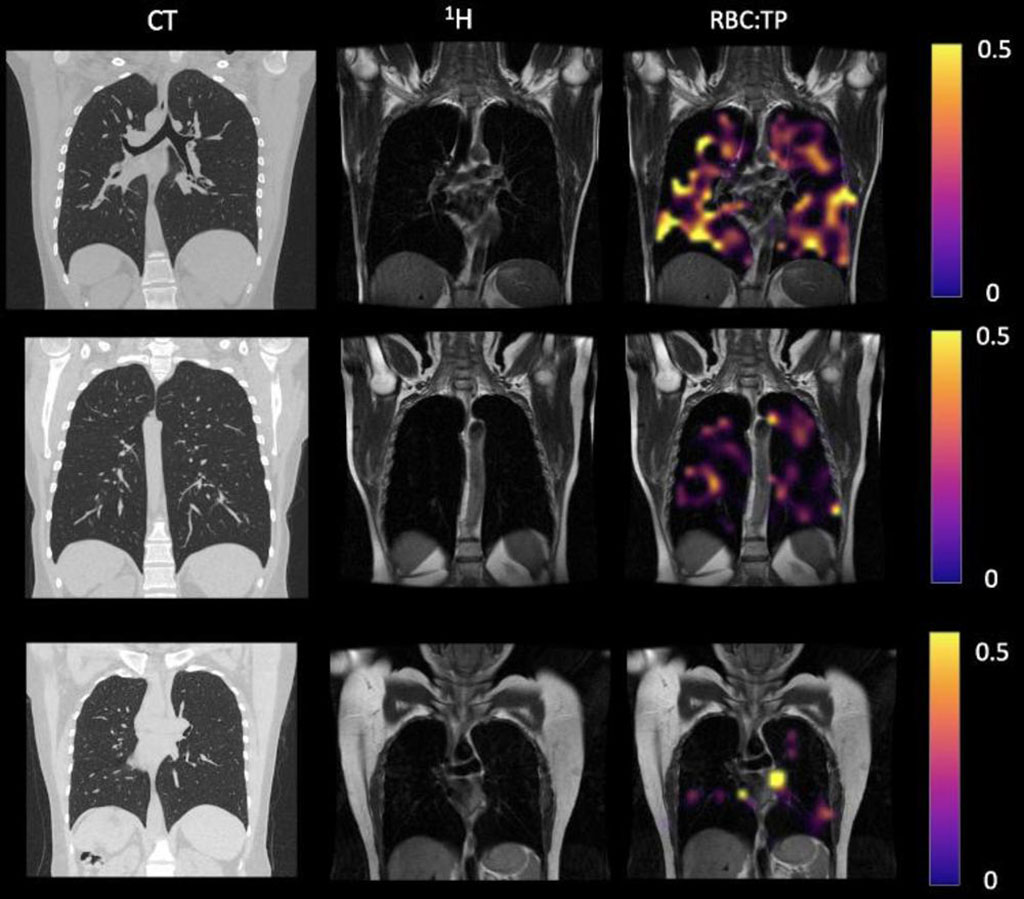

In the study by researchers at the University of Sheffield (Sheffield, UK) and University of Oxford (Oxford, UK), a specialized type of MRI (Hp-XeMRI) found lung abnormalities in non-hospitalized patients with long COVID months after initial infection. The findings provide preliminary evidence that non-hospitalized long COVID patients may have abnormalities indicative of decreased lung function that cannot be detected with conventional CT imaging. Hp-XeMRI has shown promise in detecting abnormalities of alveolar gas exchange - where oxygen moves from the lungs to the bloodstream and carbon dioxide passes from the blood to the lungs - even when CT scans and lung function tests were normal. Hp-XeMRI enables the assessment of ventilation and gas exchange into red blood cells. It provides regional information of pulmonary vasculature integrity and may be able to identify lung abnormalities not apparent on CT.

Participants were given chest CT, Hp-XeMRI, pulmonary function tests, one-minute sit-to-stand tests and breathlessness questionnaires. Control subjects underwent HP-XeMRI only. CT scans were analyzed for post-COVID lung disease severity using a previously published scoring system, and Full-scale Airway Network (FAN) modeling. Analysis used group and pair-wise comparisons between participants and controls, and correlations between participant clinical and imaging data. NHLC and PHC participants had normal or near normal CT scans.

The results showed that there were significant differences in mean red blood cell to tissue plasma ratio between healthy controls and PHC/NHLC participants, indicating potential differences in lung function. Although participants had normal or near normal CT scores, total lung diffusion capacity for carbon monoxide percentage was significantly lower between NHLC and PHC participants, potentially indicating a decrease in lung function but not structure. The researchers have said their next step is to expand their study to look at larger numbers of participants seen in dedicated post-COVID clinics at four UK centers.